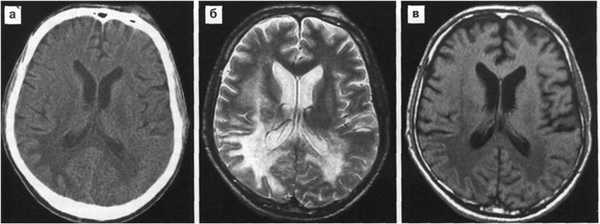

МРТ картина:

относительно симметричные диффузные или мультифокальные гиперинтенсивные изменения белого вещества в перивентрикулярной области и семиовальном центре с неровными краями, без масс-эффекта, не накапливающие контраст, либо более мелкие асимметричные очаги в белом веществе и базальных ядрах.

а-аксиальная КТ головного мозга

б,в,г -аксиальные МРТ в режимах Т2, Т1

аксиальная Т1 с контрастным усилением